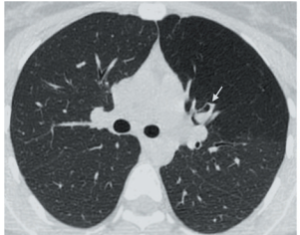

Атрезия бронха

Аномалия развития, характеризующаяся облитерацией (атрезией) просвета субсегментарного бронха в сочетании с повышенной воздушностью соответствующей части легкого.

Легочная ткань за измененными бронхами локально вздута за счет воздуха, поступающего через поры Кона из соседних участков легкого.